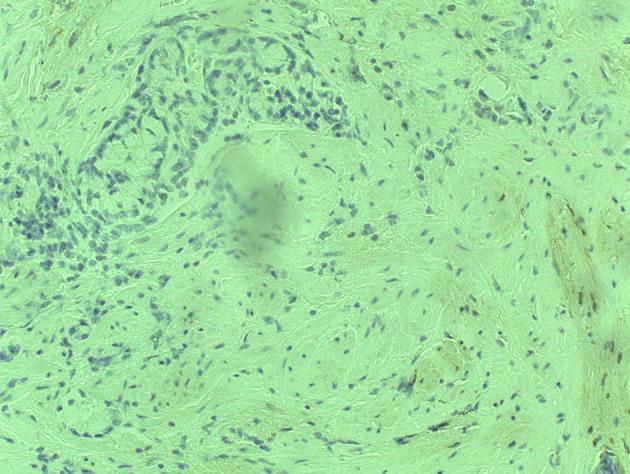

Mixed adenocarcinoid tumors are not uncommon neoplasms of appendix. The clinical presentation of these tumors is often similar to that of acute appendicitis or may present as asymptomatic. These tumors are found incidentally during histopathological examination of the resected appendix following appendectomy or other abdominal procedures. Mixed adenocarcinoids usually behave as adenocarcinomas with rapid metastasis, so prognosis depends upon how aggressive the tumor behaves. The present study reports a case of a 53-year-old male who presented with abdominal pain and fever for 1 day and underwent successful appendectomy and recovered later. Subsequently, a mixed adenocarcinoma with carcinoid features of the appendix was diagnosed by histopathological examination. Follow-up examination of the patient in 3 months revealed metastasis of carcinoma to the peritoneum with adenocarcinoma features.

混合性腺类癌肿瘤是阑尾并不罕见的肿瘤。这些肿瘤的临床表现通常与急性阑尾炎相似,或可能表现为无症状。这些肿瘤在阑尾切除术后或其他腹部手术后切除的阑尾进行组织病理学检查时偶然发现。混合性腺类癌通常表现为具有快速转移的腺癌,因此预后取决于肿瘤的侵袭性。本研究报告了一例53岁男性患者,该患者出现腹痛和发热1天,成功接受了阑尾切除术并随后康复。随后,通过组织病理学检查诊断为具有阑尾类癌特征的混合性腺癌。对该患者3个月后的随访检查发现癌转移至腹膜,具有腺癌特征。